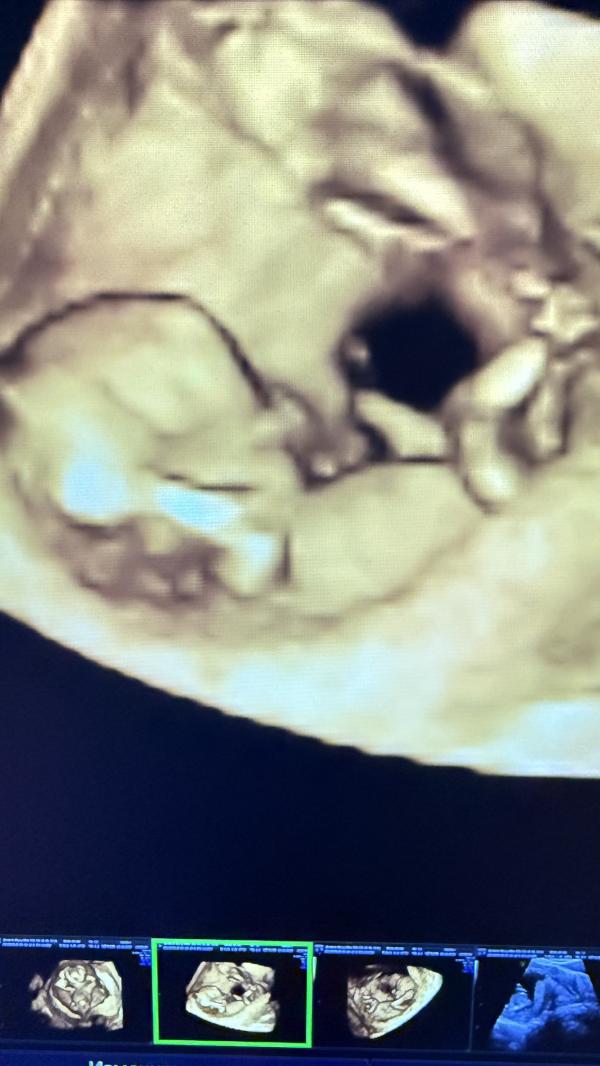

scan·В ожидании первенца

Мамочки привет )

Был ли у вас страх смерти или каких то осложнений задолго до родов ?😸 у меня сейчас 20 недель срок, а у меня уже тревожка, что я не могу спать, жуткие мысли лезут в голову. Если тоже было, Как вы с этим справились? 😭